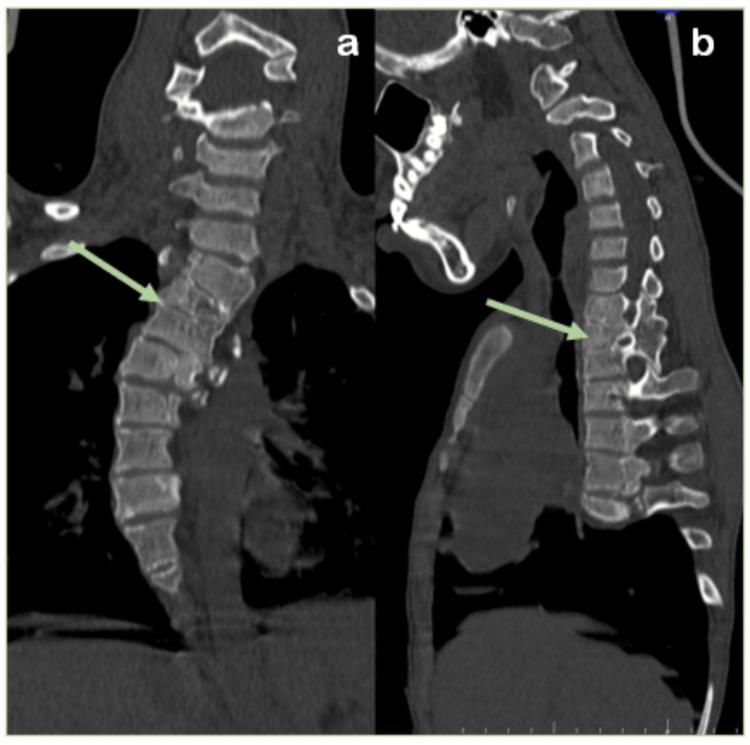

Spinal dysraphism is a spectrum of congenital anomalies caused by incomplete neural tube closure during early development, leading to spine and spinal cord defects. These can be broadly categorized into anomalies of gastrulation (including disorders of notochord formation and integration), anomalies of primary neurulation (such as premature disjunction and nondisjunction), combined anomalies of gastrulation and primary neurulation, and anomalies of secondary neurulation. This case report focuses on a 15-year-old male patient who exhibits a range of congenital spinal anomalies of spinal dysraphism spectrum, each contributing to a complex clinical picture. The primary aim of this report is to highlight the critical role of multimodal imaging in the evaluation of such conditions. Detailed imaging studies, particularly magnetic resonance imaging (MRI), are indispensable in accurately diagnosing, guiding surgical planning, and managing the diverse anomalies associated with spinal dysraphism. In this case, imaging findings were pivotal in identifying multiple congenital abnormalities, including scoliosis, butterfly vertebrae, block vertebrae, spina bifida occulta, and diastematomyelia. These conditions pose significant diagnostic and management challenges due to their varied presentations and complications.

脊柱裂是一组先天性异常疾病,由早期发育过程中神经管闭合不全引起,导致脊柱和脊髓缺陷。这些异常可大致分为原肠胚形成异常(包括脊索形成和整合障碍)、原发性神经管形成异常(如过早分离和不分离)、原肠胚形成和原发性神经管形成联合异常以及继发性神经管形成异常。本病例报告聚焦于一名15岁男性患者,他表现出一系列脊柱裂谱系的先天性脊柱异常,每种异常都导致了复杂的临床表现。本报告的主要目的是强调多模态成像在评估此类病症中的关键作用。详细的影像学检查,尤其是磁共振成像(MRI),对于准确诊断、指导手术规划以及管理与脊柱裂相关的各种异常至关重要。在本病例中,影像学检查结果对于识别多种先天性异常至关重要,包括脊柱侧弯、蝴蝶椎、融合椎、隐性脊柱裂和脊髓纵裂。由于这些病症表现多样且并发症复杂,给诊断和治疗带来了重大挑战。